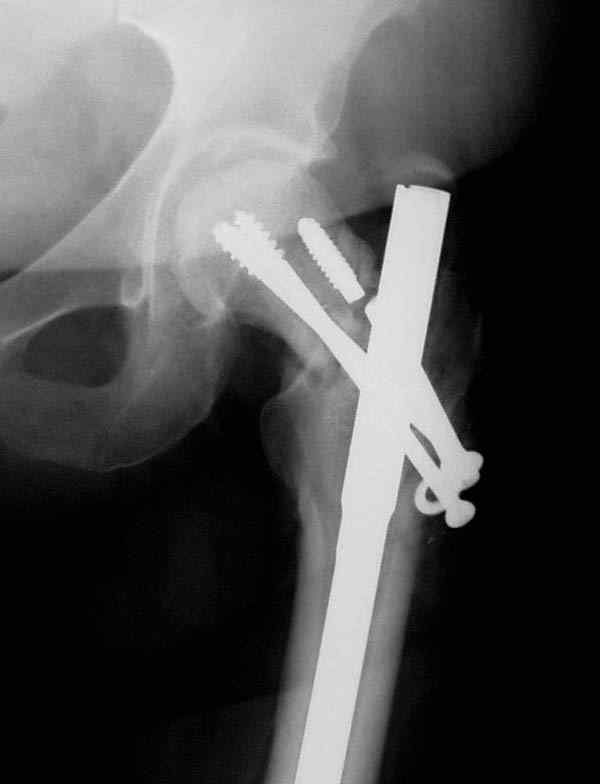

Учитывая молодой возраст больного, из всех рекомендуемых вариантов для лечения ложного сустава шейки предпочтительным является вальгусная остеотомия (на сайте имеются прежние разборы) из-за простоты исполнения и биомехнических преимуществ.

Наверно, вариант с вальгизирующей остеотомией с фиксацией blade plate или DHS более щадящий. А диафиз можно рефиксировать ретроградно. Или про эндопротезирование с очень длинной ножкой подумать.

Несмотря на пессимистические прогнозы, у молодых

коррегирующая вальгусная остеотомия является более

приемлемым.

Представленные случаи доказательства тому, что еще

имеется резервы на восстановление даже у 5-6 месячных ложных суставов шейки.